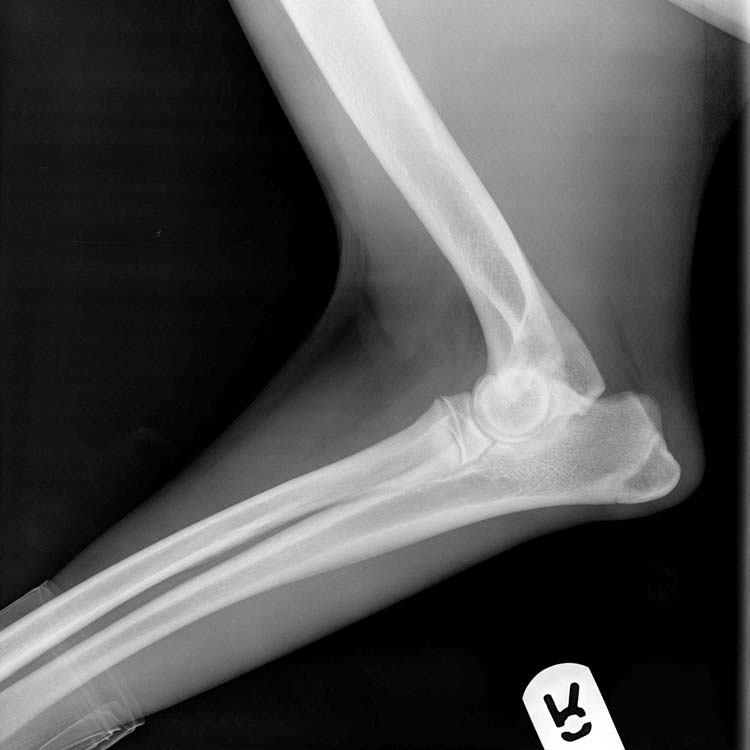

Ununited anconeal process

In growing dogs, the aonconeal process of the ulna should fuse to the remainder of the ulna by 22 weeks of age. In some dogs, this fusion fails and the anconeal process detaches and becomes loose in the joint. This can cause pain, inflammation and secondary osteoarthritis. The condition can occur sporadically in many larger breed dogs, but the most common breed to be affected is the German Shepherd Dog. If diagnosed early, surgical treatment can allow for the anconeus to fuse.